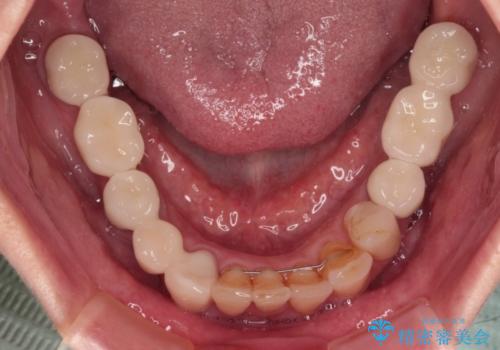

- 以前通院していた医院で、奥歯のインプラント埋入、前歯部のインビザライン矯正を行ったものの、そのまま放置してしまったとのことで来院された患者様です。

下顎前歯や上顎奥歯などをワイヤー装置により部分矯正を行い、歯列を整えた上でインプラン部分を含めてオールセラミッククラウンにて補綴治療を行うこととしました。

インプラント上の仮歯がボロボロになり、前歯に非常に負担のかかる状態であったため、早急に奥歯の仮歯を修復し、矯正治療、奥歯の補綴治療、前歯の補綴治療と順々に進めて行きました。